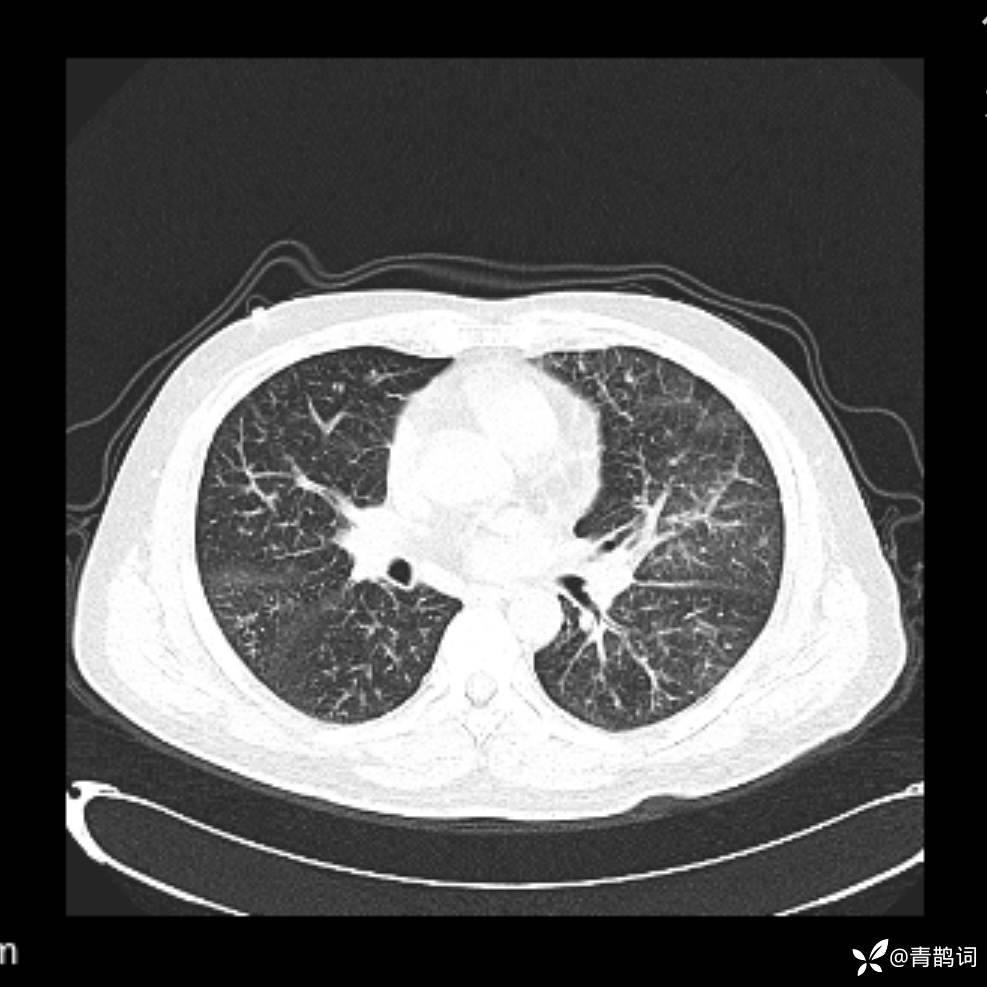

患者年龄:30岁。

患者性别:男。

简要病史:左颜面部肿胀2年,反复咳嗽咳痰,逐渐加重。

辅助检查

结合病史及影像学表现,期待评论区各位老师各抒己见~